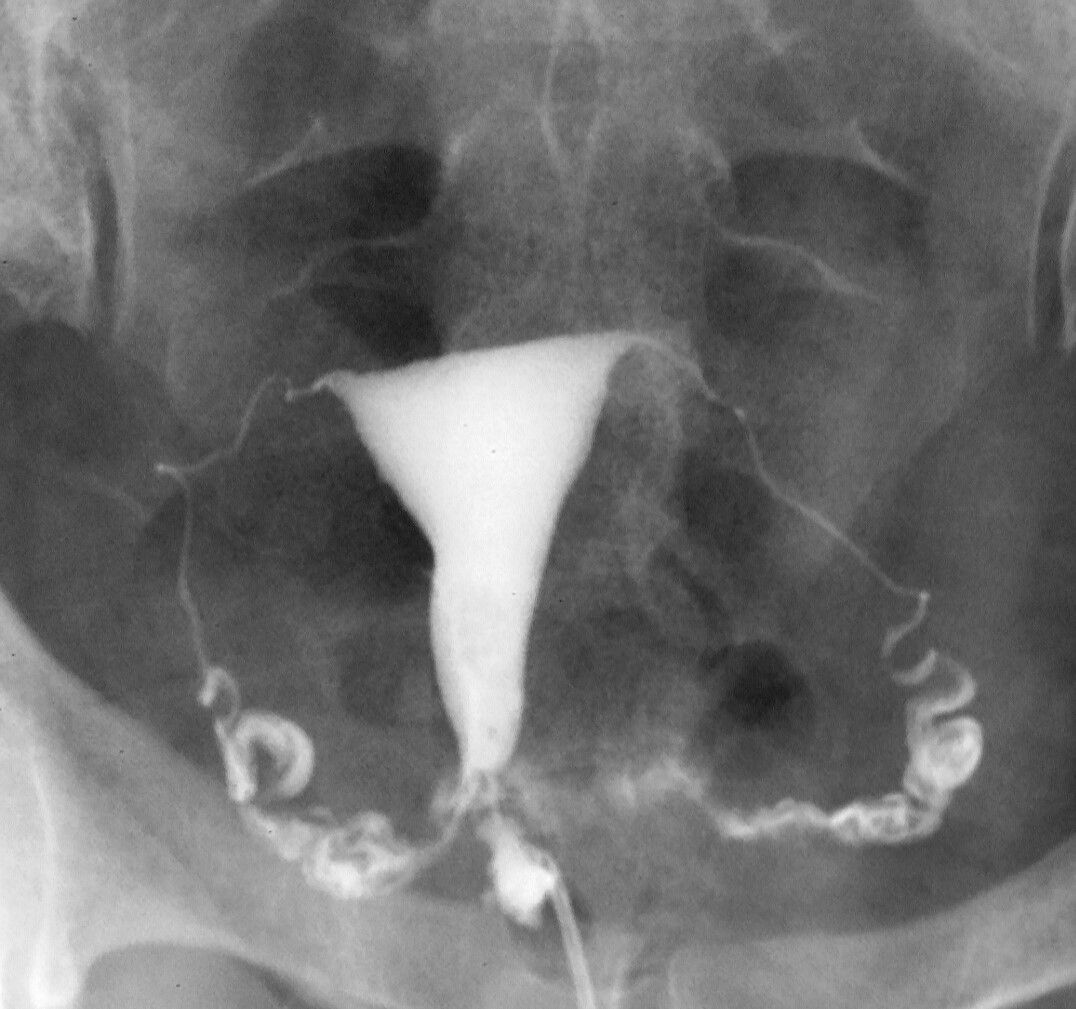

what is a hysterosalpingogram?

scan used to assess the shape of the uterus and the patency of the fallopian tubes

small tube inserted into cervix and an contrast medium is injected into the uterune cavity and fallopian tubes. x ray images taken which give an outline of the uterus and the tubes - seen on x ray and suggest tubal obstruction

infection risk - screen for chlamydia and gonorrhoea before and prophylactic antibiotics often given